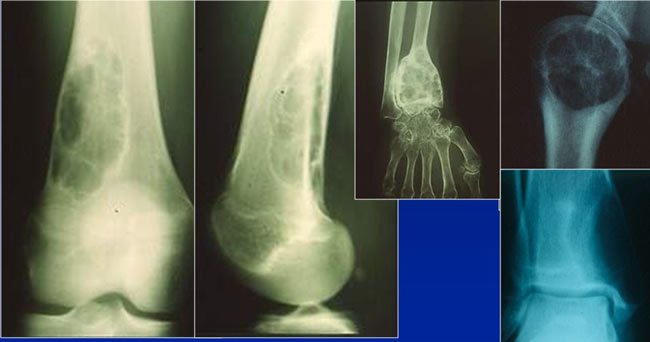

Aspect radiologique typique

Lacune épiphyso métaphysaire lytique pure

Ovalaire ou arrondie

Discrète soufflure de l'os

Parfois trabéculée

Limitée par un fin liseré condensé

Aspect tomodensitométrique typique

Persistance d'une corticale continue, parfois en pointillée

Respect du cartilage articulaire

Pas d'envahissement des parties molles

Autre Aspect radiologique typique

Tumeur épiphyso-métaphysaire lytique.

Tumeurs à cellules géantes de l'astragale

Homme de 21 ans.

Tumeur à cellules géantes active

Limites imprécises.

Corticales soufflées.

Tumeurs à cellules géantes Agressives

Destruction corticale.

Atteinte des parties molles.

Fracture.